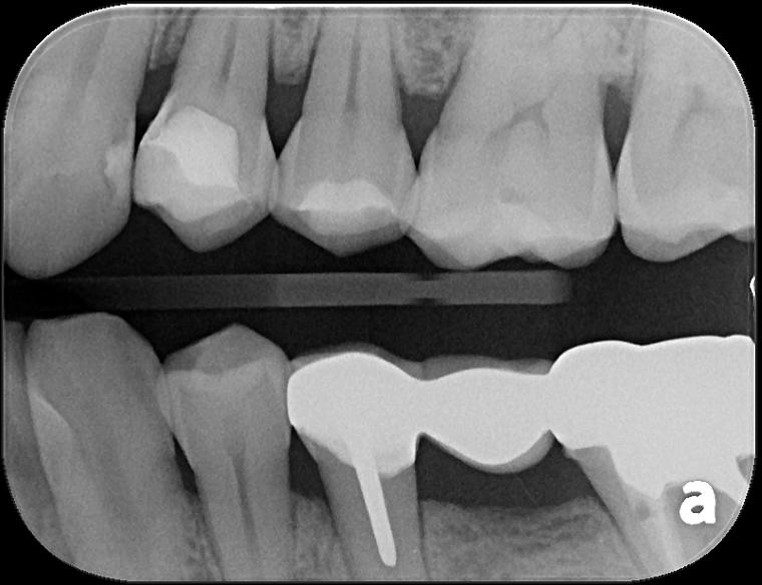

治療前,銀粉導致滲透

蛀牙未至牙髓